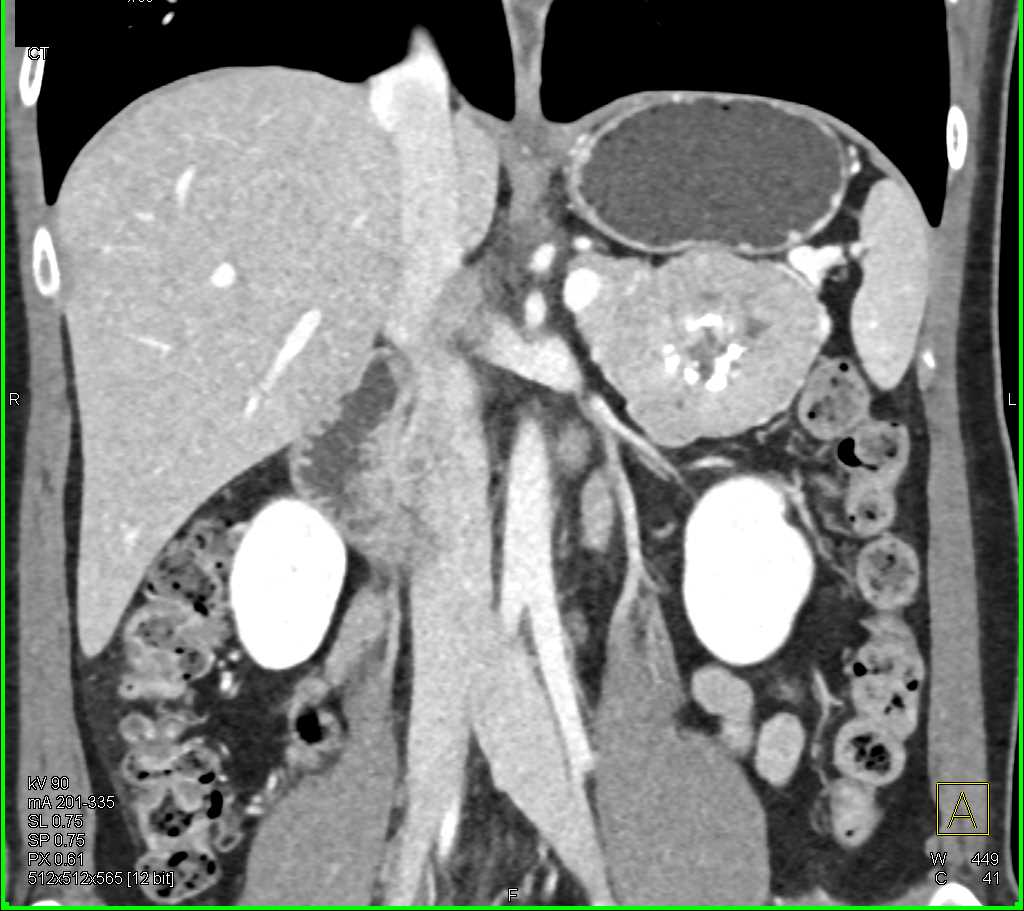

Neuroendocrine Tumor Pancreas